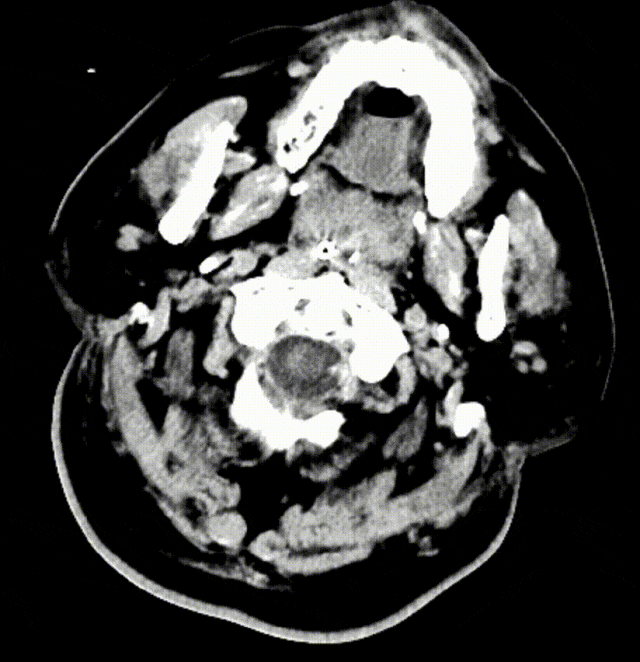

图5. 术前左椎正位:左椎起始部闭塞

图6. 右侧椎动脉正位造影:右椎V4段发育不良

图7. 尝试开通左侧椎动脉

图8. 开通失败后造影

综合术前辅助检查,(Core+pen)/Core=3.58;Pen>15ml;Core<70ml(图3);发病时间小于24小时,存在取栓指征,但是当地医院手术经验告诉我们左侧椎动脉慢性闭塞,且开通异常困难,常规手术方案很难成行,术前制定合理且可行的手术方案至关重要。方案1:仍采用左侧椎动脉+基底动脉取栓的正向开通方案,可能会继续浪费大量时间,甚至最后以失败告终。方案2:采用右侧椎动脉入路,由于右侧椎动脉V4段发育不良,当地医院已尝试过超选,证实无法通过V4段至基底动脉建立取栓通路。方案3:既往有文献报道开颅椎动脉直视下穿刺取栓,虽然方案可行,但我院无类似手术经验,贸然尝试风险难以把控。方案4:回顾当地医院取栓影像资料,发现双侧颈内动脉后交通呈胚胎型,是否可能通过后交通跨循环逆向超选至基底动脉取栓。患者平卧DSA床,全麻插管成功后,用碘伏常规消毒手术区皮肤,铺无菌巾单。取双侧股动脉为穿刺点,于14时00分seldinger法穿刺成功后分别置入8F穿刺鞘和5F 短鞘。行全脑血管造影显示左侧椎动脉起始部闭塞,颈升动脉通过肌支代偿V2及以远的椎动脉血流,右侧椎动脉V4段发育不良,单纯供应右侧PICA,双侧后交通动脉胚胎型。(图9,图10)首先我们仍尝试传统入路进行超选左侧椎动脉,发现左侧椎动脉开口闭塞,斑块质地坚硬,微导丝微导管无法通过。短暂尝试无果后,迅速改为右侧椎动脉入路,发现将微导丝塑型成“J”型或成袢,均无法到达右侧椎动脉V4段,遂果断决定采用跨循环取栓方案。将5F VERT造影导管超选至左侧锁骨下动脉,进行正向血流监测。6F 90cm长鞘(cook)及5F 125cm Navien导管在泥鳅导丝带领下超选进入右侧颈内动脉岩骨段。随后将Rebar18微导管在Synchro2微导丝带领下超选至大脑中动脉,并将Navien带领至右侧颈内动脉交通段。微导丝微导管回撤至颈内动脉,路图下Synchro2微导丝带领Rebar18逐步通过右侧后交通动脉,再在透视下经右侧大脑后动脉P1段盲超选至基底动脉下段。(图11-13)手推造影确认Rebar18微导管已突破血栓段,并在基底动脉真腔内。(图14)经Rebar18释放一枚solitaire FR支架(4mm×20mm)覆盖血栓段。SWIM技术负压下抽拉支架1次,抽拉过程中时刻注意系统张力,逐步回撤支架同时适度回撤Navien释放张力,以保证Navien贴近后交通开口而不向后交通动脉内继续深入。撤出支架后,Navien原位保持负压约30秒。(图15)造影复查见基底动脉及其分支再通,支架取出少量血栓(图18)。于14时45分达到远端血流mTICI3级,10分钟后复查造影显示血管通畅,于14时55分末次造影见远端血流维持mTICI3级。(图16,17)术中Dynamic CT未见明显术区出血(图19)。遂缝合穿刺点,结束手术。手术顺利,术中病人情况稳定。术末血压115/58mmHg,脉搏70次/分,呼吸12次/分,氧饱和度100%。术毕送重症监护室。图9. 双侧椎动脉造影:左侧椎动脉起始部闭塞,左侧颈升动脉肌支和右侧椎动脉通过脊髓支代偿V2及以远的椎动脉血流;右侧椎动脉V4段发育不良,单纯供应右侧PICA